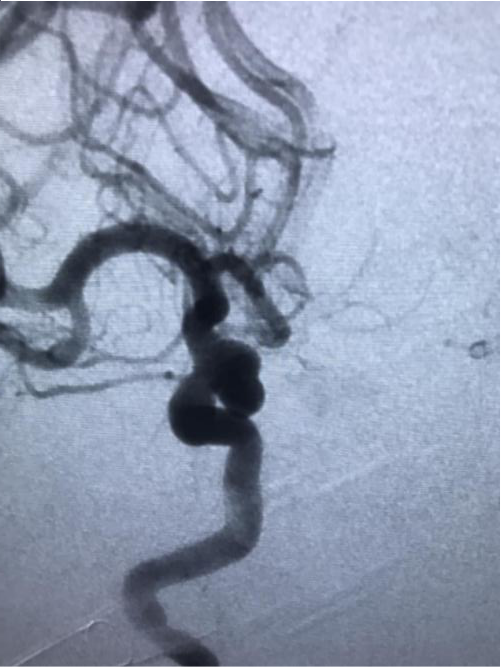

(治疗前二维造影)

入院后第二天,赵师傅被送入杂合手术室,脑血管病组团队医师们登台手术。医生们从赵师傅右股动脉穿刺,将导丝从股动脉、腹主动脉、胸主动脉一路插至颅内载瘤动脉,再运用微导管技术将弹簧圈送到动脉瘤腔内,栓塞瘤腔,在主干血管内置入一枚支架,稳固弹簧圈的同时保留了正常血管的血流。经两个小时手术,赵师傅脑内的动脉瘤被完全填塞封堵。